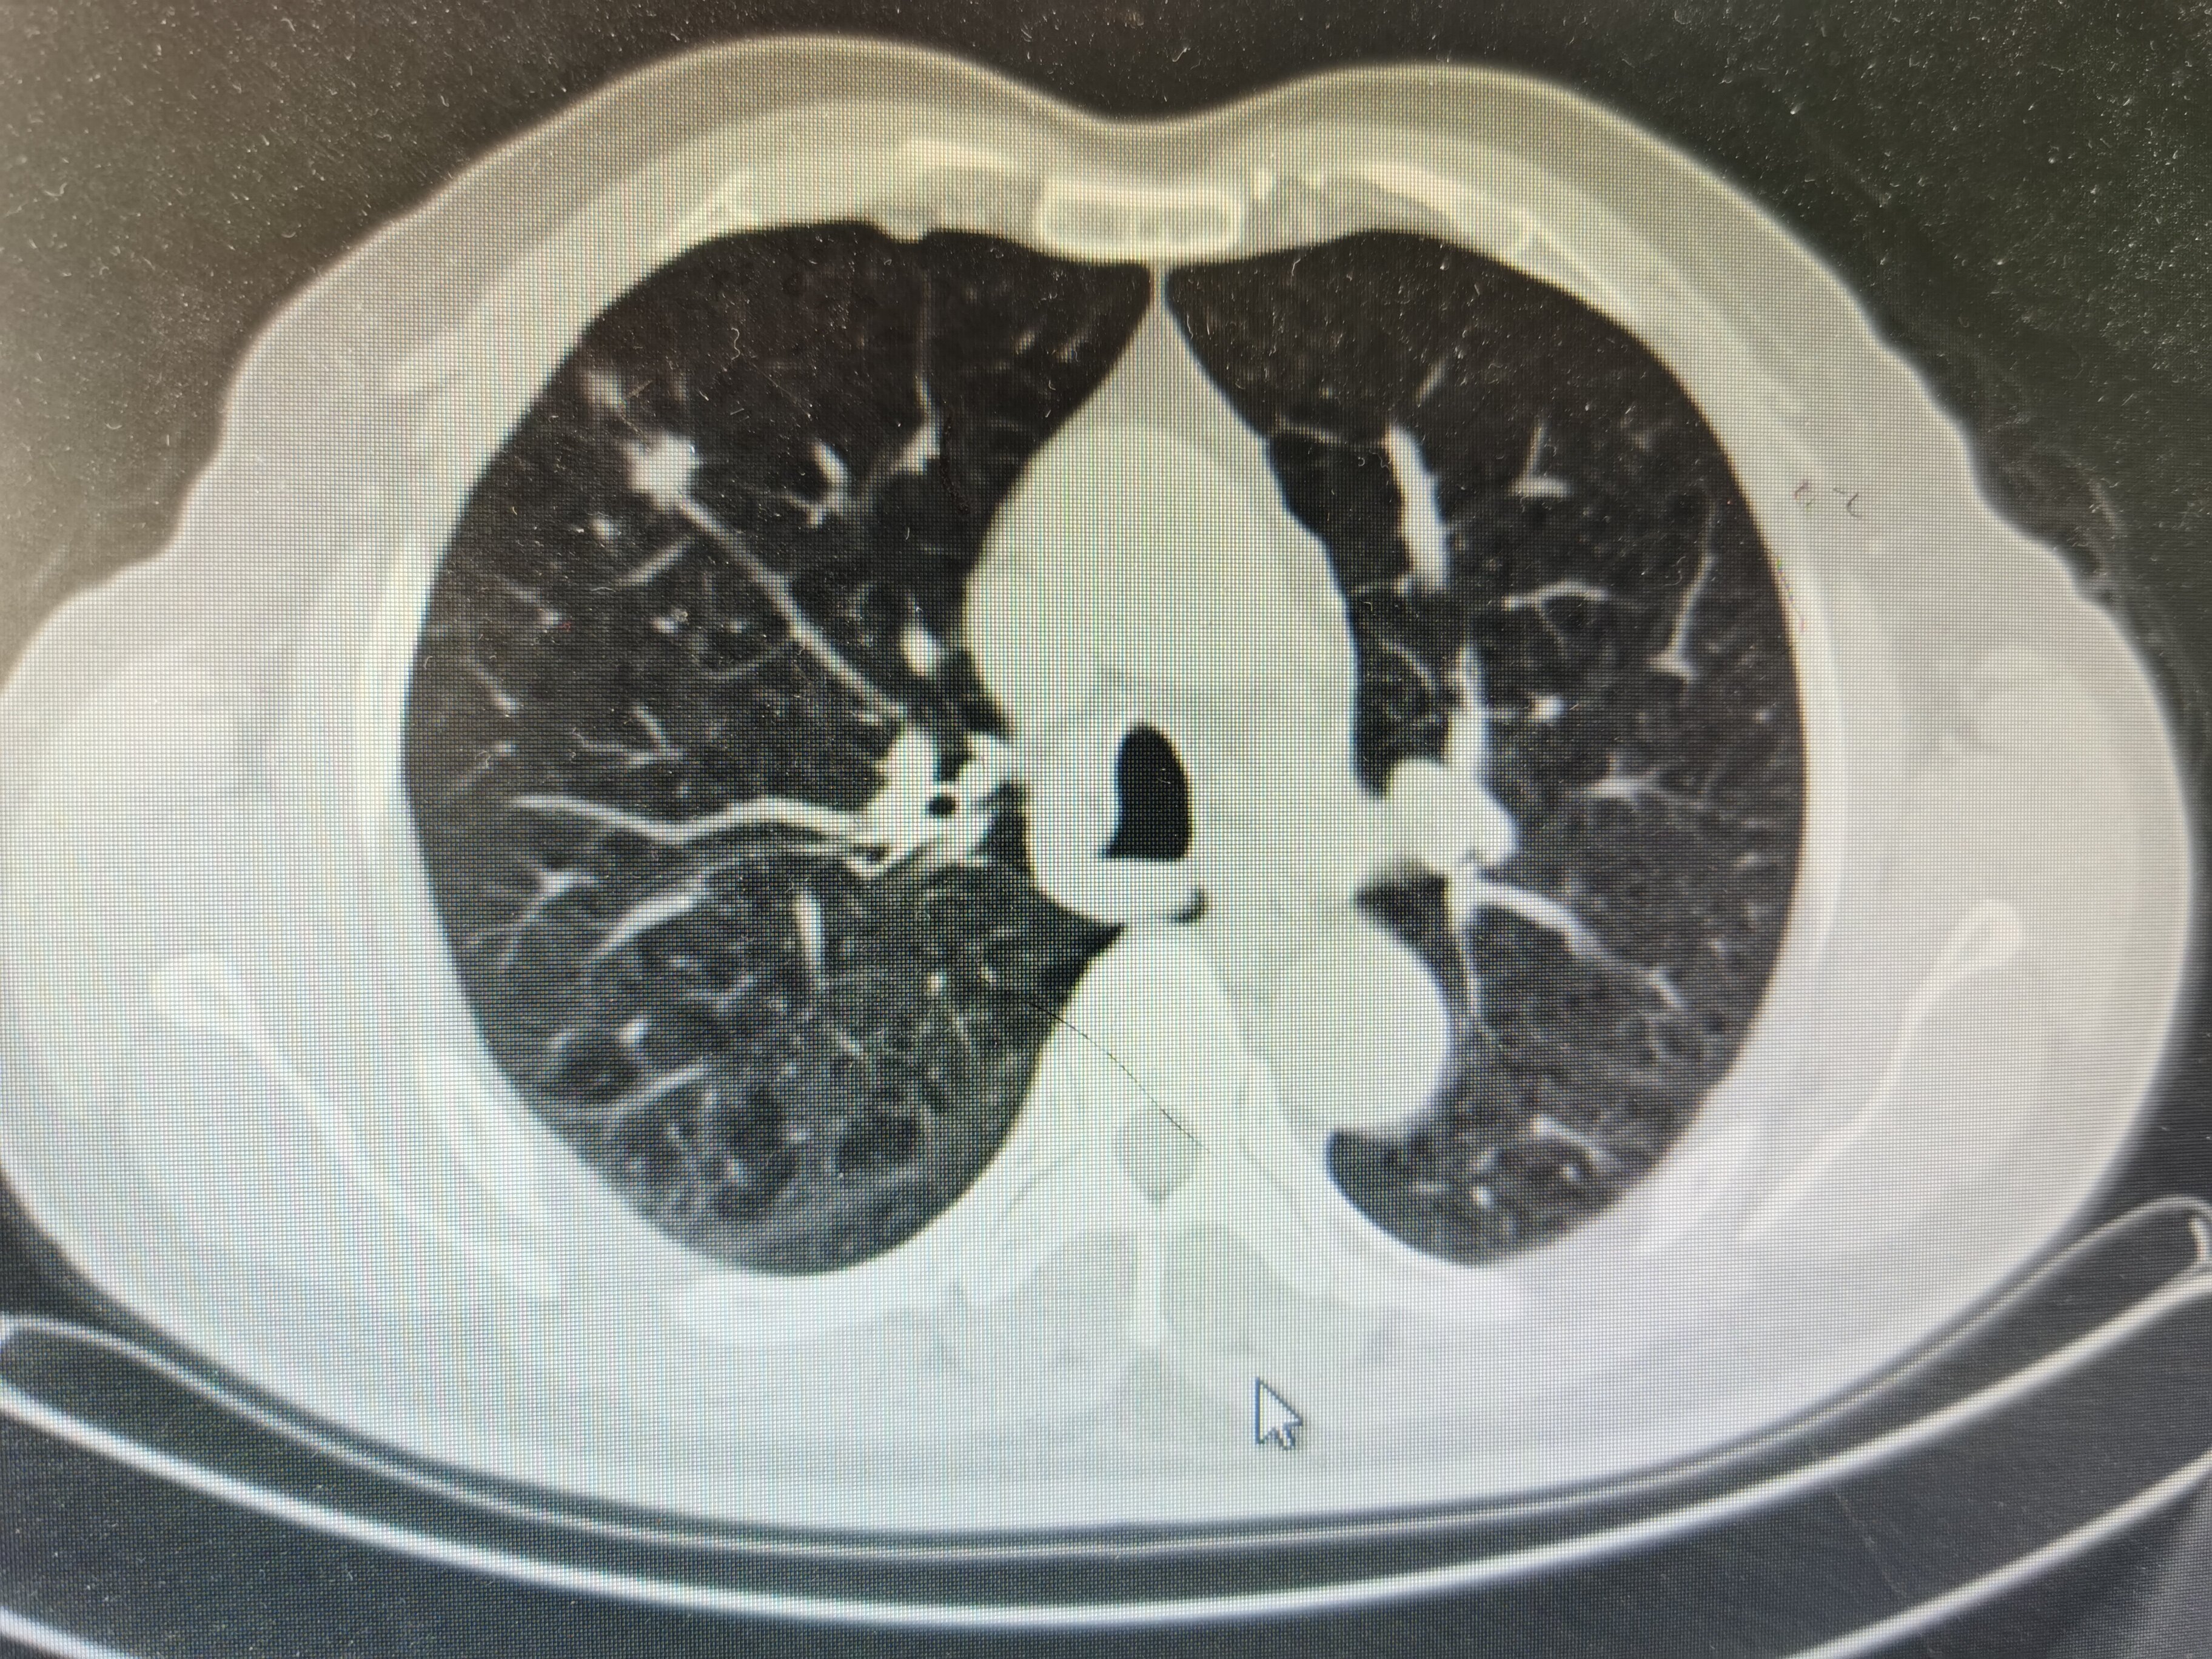

肺结节是指在肺部影像学检查中观察到的直径小于或等于30毫米的局部、类圆形、密度增高的实性或亚实性阴影。这种术语并不代表一种特定的疾病,而是对一种影像学表现的描述。

①结节大小:直径大于20毫米的实性结节,或大于8毫米的部分实性结节,属于高危结节。

②结节形状:边界不清、轮廓不规则的结节,恶性可能性较大。

③结节密度:密度不均匀的结节,恶变概率更高。

④结节变化:定期复查中,如果结节直径增大,密度比例增加,需高度警惕。